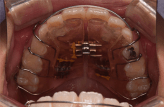

小学生からのマウスピース型カスタムメイド矯正歯科装置(製品名インビザライン 完成物薬機法対象外)は小学生のために開発された新しいマウスピース装置です。大人に比べると、まだ高さの低いお子さんの歯にもぴったりとフィットするように開発されました。また、アタッチメントと呼ばれるマウスピース型カスタムメイド矯正歯科装置(製品名インビザライン 完成物薬機法対象外)による矯正治療に必要不可欠な補助装置も子ども専用に開発されました。小学生からのマウスピース型カスタムメイド矯正歯科装置(製品名インビザライン 完成物薬機法対象外)は、小学生でも取り扱いやすくストレスなくお使いいただけるような特別な製品となっております。